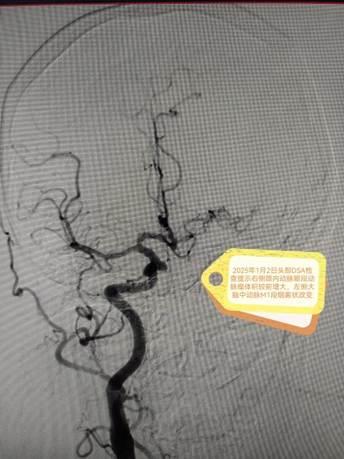

患者李阿姨3年前确诊左侧颈内动脉起始部闭塞,伴有左侧大脑中动脉M1段烟雾状改变及右侧颈内动脉眼段动脉瘤。由于病情稳定,无明显症状,未达到手术指征,初期采取密切随访观察。202512日,李阿姨前来复查时DSA显示右侧眼段动脉瘤增大,诊断为“烟雾病综合征、左侧颈内动脉闭塞、右侧眼段动脉瘤”。面对颅内外血管多发病变与动脉瘤进展的双重威胁,手术难度与风险极高,家属一度陷入焦虑。

术前DSA结果